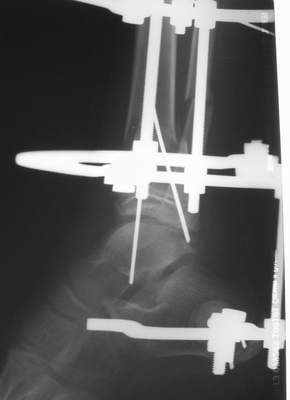

Вытяжение

|

Нашел в комп-ре схожий случай:

1) з/репозиция, 2) фиксация 2 спицами, 3) аппарат, 4) фиксационные

спицы удалены...

См. аттачт.